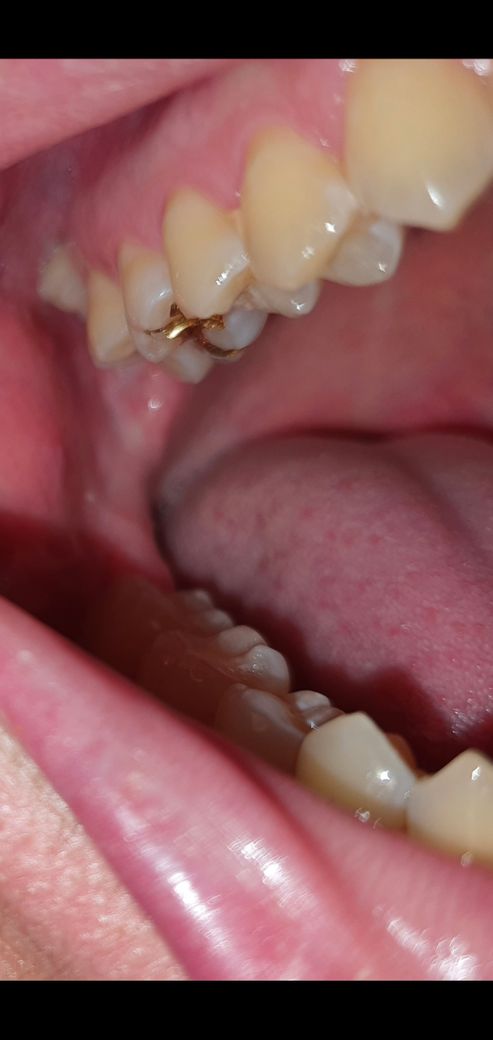

이렇게 난 사랑니 뽑아야 하나요?

통증은 없습니다.

썩을까봐 무서워서 매일 양치할때 신경써주고, 치실 및 리스테린 사용까지 합니다.

이거 뽑아야 하는 이인가요?

• 1번 째 사진

맨 뒤에 있는 치아는 사랑니이므로 이를 발치하는 것이 맞습니다. 결국 해당 치아에 의해서 앞쪽 어금니까지 손상되거나 충치가 발생할 수 있으므로 미리 발치하는 것을 추천드립니다. 해당 사랑니는 발치 난이도가 높아보이지 않습니다. 따라서 가까운 시일내에 발치할 것을 추천드립니다.

사랑니 자체는 크게 문제가 있어 보이진 않습니다. 하지만, 관리가 잘안되서 그쪽에 염증이 생기는게 반복되면 발치를 하셔야될수도 있습니다.